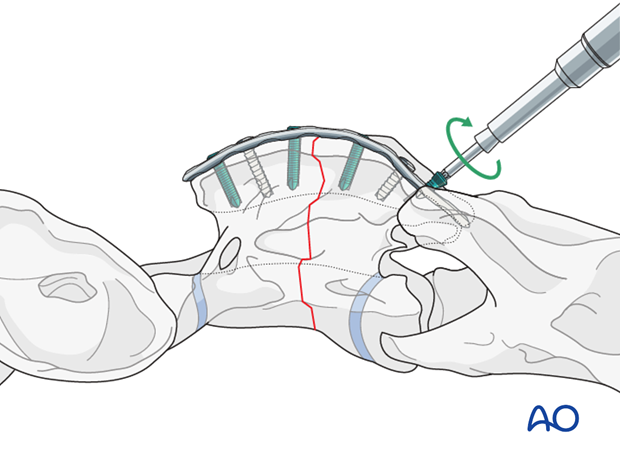

The use of the locking compression plate (LCP) is preferred for fracture fixation of the vertebrae. According to the size of the patient, a small or broad 3.5/4.0 or 4.5/5.0mm LCP is used.

With the reduction forceps in position, the appropriately sized plate is applied on the dorsal spinous process.

One cortex screw is inserted into each fragment in load fashion. The correct length of the screws is determined with the help of fluoroscopy.

The remaining holes are filled with locking-head screws.